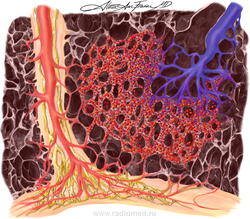

Легочный капиллярный гемангиоматоз